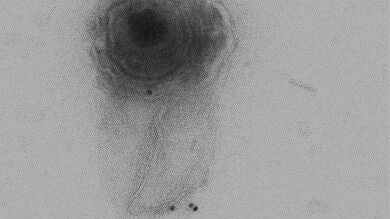

Las microvesículas (MVs) son VEs que se forman a partir de la membrana celular. Los últimos resultados del grupo de López Guerrero, publicados en la revista Journal of Virology, muestran el aislamiento y caracterización de las MVs producidas por células oligodendrocíticas infectadas por HSV-1, y se estudian su relación con la salida viral.

“Por primera vez nuestros resultados han mostrado que HSV-1 puede salir de la célula dentro de MVs. Además, hemos encontrado que estas MVs con viriones en su interior, eran capaces de ser endocitadas por otras células y llevar a cabo de este modo una infección productiva”, señala Bello-Morales.

Según el trabajo, las MVs parecen proceder de la ruta autofágica –mecanismo de regulación de la degradación proteica y de orgánulos celulares–, dado que mostraron marcadores de dicho proceso autofágico, como la proteína LC3B.

Según los autores, la extrapolación del estudio a otros tipos celulares mostró que la salida viral mediada por MVs es dependiente del tipo celular, dado que en la línea de melanoma humano se encontraron estructuras sugerentes de un proceso de salida viral mediante la evaginación de la membrana celular conteniendo viriones con envuelta encerrados en vesículas.

Estas estructuras, que mostraron viriones rodeados por tres envueltas, no fueron sin embargo observadas en la línea celular oligodendrocítica HOG.